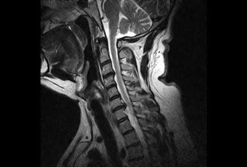

2.頚椎椎間板ヘルニア

椎間板は中心が柔らかい髄核と、その周りを繊維性軟骨組織からなる繊維輪から構成され、椎間板は椎骨間で衝撃を吸収してクッションのような役割を果たします。

クッションの表面が破れた状態、すなわち椎間板・線維輪に亀裂が入って内部の髄核が飛び出した状態が椎間板ヘルニアです。

椎間板機能の異常は頸部痛などを引き起こしますが、飛び出した髄核は頸椎内部を走行している脊髄や神経根といった重要な神経組織を圧迫し、手足のしびれや痛み・運動麻痺などのさまざまな神経症状を引き起こします。